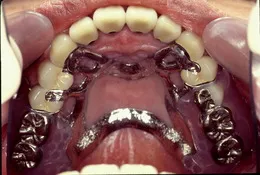

部分入れ歯(パーシャルデンチャー)

部分入れ歯とは一部の歯を失った部位に取り外しの入れ歯を用いて治療する方法です。

残っている歯に特殊な金具を使って入れ歯を取り付けます。部位によっては金具が見えることもあります。

「部分入れ歯は使いづらい?」こんな不安をお持ちの方や実際に不満を感じている方も多いかもしれません。現在ではインプラントもかなり普及していますが、インプラントと部分入れ歯とを比べると正直なところ使いやすさ、咬みやすさではインプラントに軍配が上がります。しかし、部分入れ歯でも工夫して精密に仕上げることによって驚くほど使いやすいものにできるのです。

当院での部分入れ歯の特徴:残っている歯を診査し徹底した治療を行います。歯を失い始めたらもうあるがままでは健康な状態を保てません。抜いて傷が治ったらすぐに入れ歯を入れることは他の歯の寿命も短くしてしまうかも知れません。

金具がかかる歯の整備をします。おもにかぶせ物を使って環境整備を行います。

精度の良い金属フレームを採用しています。当院では日本の金属フレーム製作のパイオニアである川島哲氏が製作したものを使用しています。精度が不十分なものは再製作していますので安心しておまかせ下さい。

(部分入れ歯を入れるためには残っている歯に前処置を行い整備が必要となります。)

(残っている歯にかぶせ物等で整備しておくとぴったりと入れ歯が適合して『動かない入れ歯』を装着することができます。)

(金属フレームの入れ歯は薄くて強度があるためお口の中での異物感をあまり感じません。)

(残っている歯の整備には『入れ歯の設計能力』が必要です。)

(まさに『匠の技』が活かされた金属フレームの部分入れ歯です。)